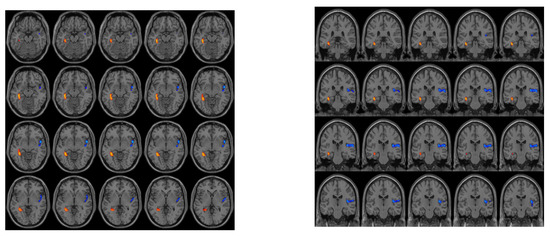

| Brain Area (AAL) | VOXEL | Peak MNI Coordinate | Peak | ||

|---|---|---|---|---|---|

| right insula | 257 | 50 | 6 | −6 | −5.0958 |

| left hippocampus | 70 | −36 | −40 | −8 | 4.8948 |